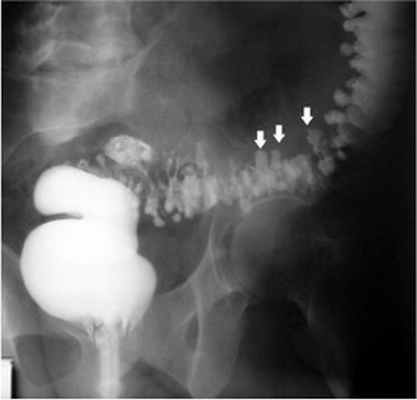

При рентгеноскопии желудка и двенадцатиперстной кишки: акт глотания не нарушен. Пищевод свободно проходим, определяется значительных размеров (до 7 см) грыжа пищеводного отверстия диафрагмы с выраженным рефлюкс-эзофагитом и забросом содержимого желудка в дистальный отдел пищевода, увеличивающаяся в размерах в положении лежа на животе. Желудок обычно расположен, натощак содержит слизь и жидкость. Складки слизистой утолщены, извиты, по задней стенке и большой кривизне в кардиальном отделе образуют зубчатость. Привратник свободно проходим, отмечается пролабирование слизистой желудка в луковицу двенадцатиперстной кишки. В нисходящей ветви петли двенадцатиперстной кишки определяется дивертикул на ножке размером 3 см с большим количеством слизи в нем (рис. 2). Луковица двенадцатиперстной кишки раздражена, бариевая взвесь очень быстро проходит ее, отмечается обратный заброс бариевой массы в желудок. Заключение: скользящая грыжа ПОД. Рефлюкс-эзофагит. Гастрит. Дуоденит. Дуоденогастральный рефлюкс. Дивертикул петли двенадцатиперстной кишки с признаками дивертикулита. От проведения ЭГДС пациентка категорически отказалась.

![Рентгенограмма дивертикула петли двенадцатиперстной кишки]()

Рис. 2. Рентгенограмма дивертикула петли двенадцатиперстной кишки.